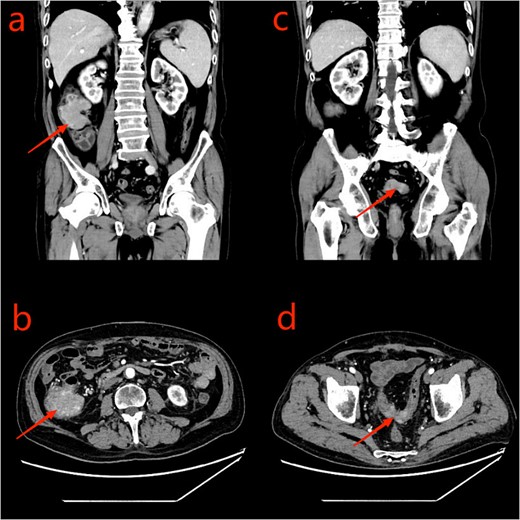

Given the patient’s unsuitability for immediate radical surgical resection, the patient was administered monotherapy with capecitabine to control tumor progression. During an outpatient follow-up, a slight enlargement of the tumor was observed in the ascending colon region. To further understand the patient’s condition, he was readmitted to the hospital, to undergo laboratory tests, serum CEA: 26.10 ng/ml, uric acid: 447 umol/L, and platelet levels were normal. Repeated enhanced CT scanning of the abdomen revealed complete recovery from the obstruction (Fig. 3). To ascertain the nature of the ascending colon tumor,a repeat colonoscopy examination through colostomy showed the sigmoid and ascending colon tumor. The biopsy of the ascending colon tumor revealed an adenocarcinoma (Fig. 4). Given the patient’s concomitant small B-cell lymphoma and primary thrombocytopenia, surgical treatment was decided after a multi-disciplinary team discussion.

CT scan of the abdomen and pelvis: a and b: ascending colon tumor; c and d: sigmoid tumor.